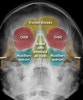

(2) McGrigor-Campbell lines

| Red line Passes through the zygomatico-frontal sutures and across the upper edge of the orbits Orange line Follows the zygomatic arch, crosses the zygomatic bone and follows the inferior orbital margins to the opposite side Green line Passes through the condyle (1) and coronoid process (2) of the mandible and through the lateral and medial walls of the maxillary antra on each side Midline Used to assess symmetry |